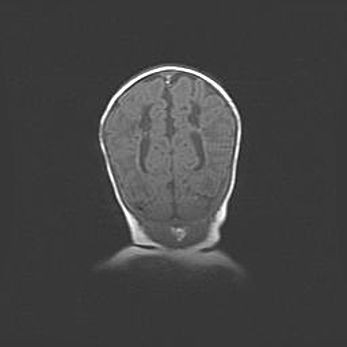

Наружная гидроцефалия с возможной атрофией височных областей.

Возраст: 28 дней

Вес: 3670 г

Пол: мужской

Окружность головы: 38 см

Срок гестации: 40 недель

Гидроцефалия головного мозга у новорожденных – это заболевание, которое характеризуется скоплением избыточного количества спинномозговой жидкости в желудочковой системе головного мозга в результате затруднения её перемещения от места выработки к месту поглощения в кровеносную систему или вследствие нарушения абсорбции. При открытой наружной форме гидроцефалии у новорожденных расширяются и переполняются субарахноидные пространства.

При нормотензивных  формах,  которые,  как  правило,  являются  следствием  перенесенных ишемических  повреждений  паренхимы  мозга,  возможно  сочетание микроцефалии  с нормотензивной гидроцефалией. В основе данных изменений лежит атрофия больших полушарий с преимущественной  локализацией  в  лобно-височных  областях.